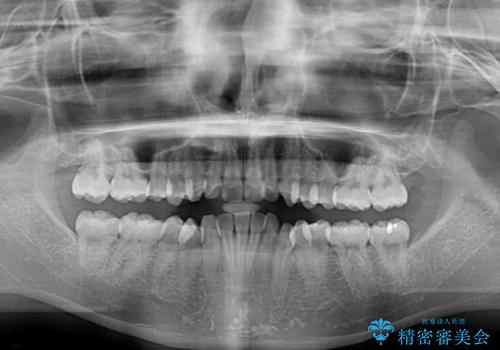

- 口を閉じたときに飛び出してしまう上顎前歯を気にして来院された患者様です。

下顎はデコボコが気になっていたため、上下左右第一小臼歯4本を抜去して、ワイヤー装置にて口元の突出感を改善するよう矯正治療を行うこととしました。